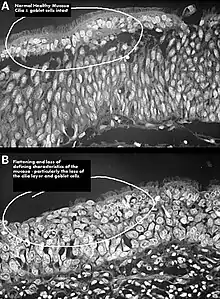

Squamous metaplasia of nasal respiratory epithelium.